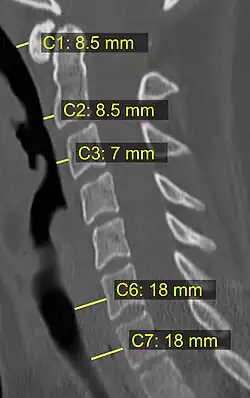

CT scan or X-ray images are evaluated for the presence or absence of directly visible fractures. In addition, indirect signs of injury by the vertebral column are incongruities of the vertebral lines,[11] and/or increased thickness of the prevertebral space:[12]

12. ^ a b Rojas, C.A.; Vermess, D.; Bertozzi, J.C.; Whitlow, J.; Guidi, C.; Martinez, C.R. (2009). "Normal Thickness and Appearance of the Prevertebral Soft Tissues on Multidetector CT". American Journal of Neuroradiology. 30 (1): 136–141. doi:10.3174/ajnr.A1307. ISSN 0195-6108. PMC 7051716. PMID 19001541.